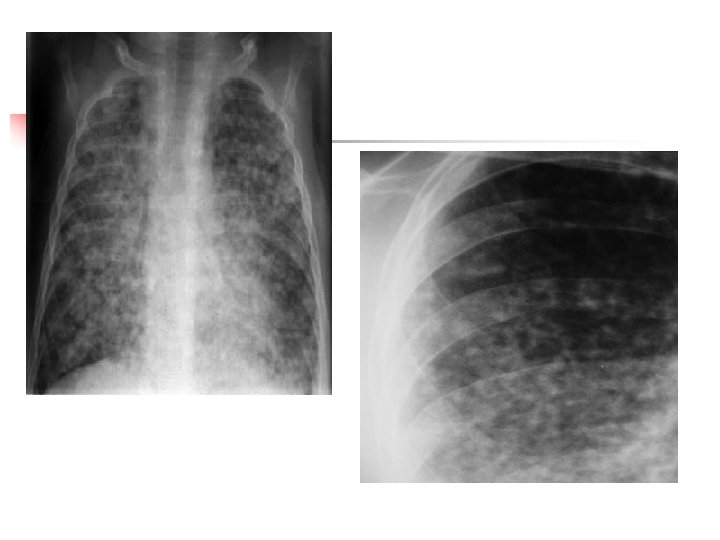

Opacités micronodulaires (miliaires) ♦ Dissémination par voie hématogène d'un processus infectieux ou tumoral. ♦ Leur taille et 1 à 3 mm de diamètre, uniforme et leurs contours sont nets. ♦ Prédominance aux bases vascularisation plus importante.

Infiltration micronodulaire de type hématogène Miliaire Tuberculose Miliaire carcinomateuse